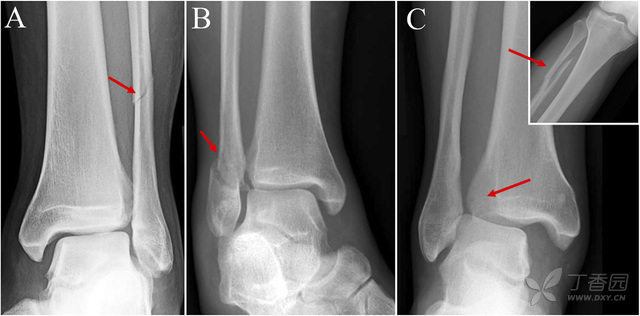

jbjs概念回顾:踝关节下胫腓联合韧带损伤

图片尺寸640x316

有时候外踝骨折合并下胫腓联合损伤脚踝扭伤后的症状由轻到重各不相同

图片尺寸3264x2448